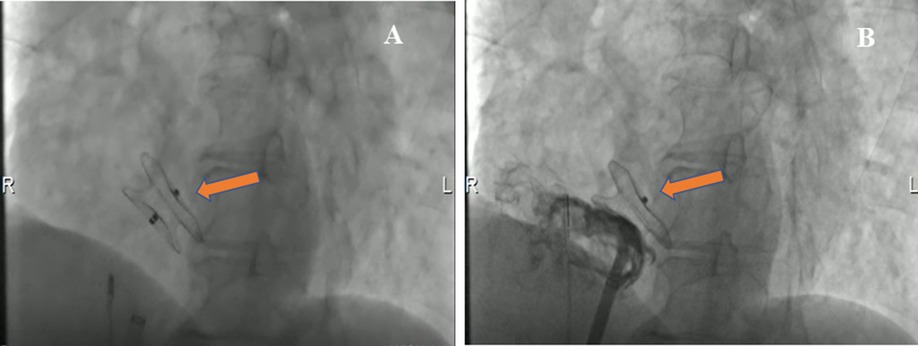

The patient underwent an ASD percutaneous occlusion under the guidance of intracardiac echocardiography (ICE) (Supplementary Movie III). During the operation, the LASH with ASD could be visualized by ICE from different angles. After balloon sizing, an 18 mm septal occluder device (Pushi, Shanghai) was successfully deployed (Figures 3A,B and Supplementary Movie IV). The occluder embraced the thick lipomatous cephalad rim and the thin “normal” caudal rim of the fossa ovalis. The left-to-right shunt disappeared, and no procedural complications, such as erosion or embolization, were observed. The patient was asymptomatic postoperation and followed up in an outpatient clinic (Supplementary Figures 1A–C). The atrial septum no longer increased in thickness. The systolic pulmonary artery pressure was ≈25.8 mmHg after ASD closure.

Figure 3. Cardioangiography (CAG) images demonstrating the closure with a Pushi septal occluder device. (A) CAG image visualized the position of a Pushi septal occluder device during the operation (arrow). (B) CAG image revealed the position of the septal occluder device was good, and there was no shunt between the left atrium and the right atrium after occlusion (arrow).